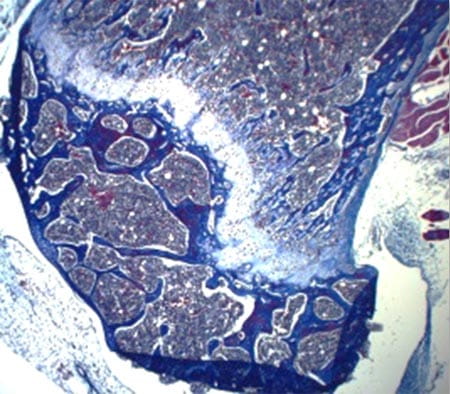

Hematopoiesis takes place in specialized bone marrow microenvironment, called ‘niche’. The stem cell niche is composed of several cell types that produce regulatory cytokines and offer physical support that are essential for HSC localization, self-renewal and differentiation.

The fundamental issue in stem cell biology that has yet to be understood is how the hematopoietic stem cell niche is generated during embryogenesis and how it controls HSC functions at a molecular level. Mesenchymal stem cells are multipotent stem cells that are thought to give rise to several cell types that constitute the HSC niche, including osteoblasts, stromal cells and adipocytes. However, how they do so in vivo and whether this is important for the development of the hematopoietic system is still largely unknown.

The lab is interested in understanding how signaling pathway controls MSC fate and development into a functional stem cell niche. We have recently discovered that the Rho GTPase regulator p190-B RhoGAP is also a critical regulator of mesenchymal stem cell fate differentiation (at least to chondrocytes, osteoblasts and adipocytes) and functions that are necessary for hematopoietic tissue homeostasis. The objectives of this program research are to investigate how p190-B regulates bone marrow niche development and to identify the signal pathways that are responsible for its effect and how this affects hematopoietic development.